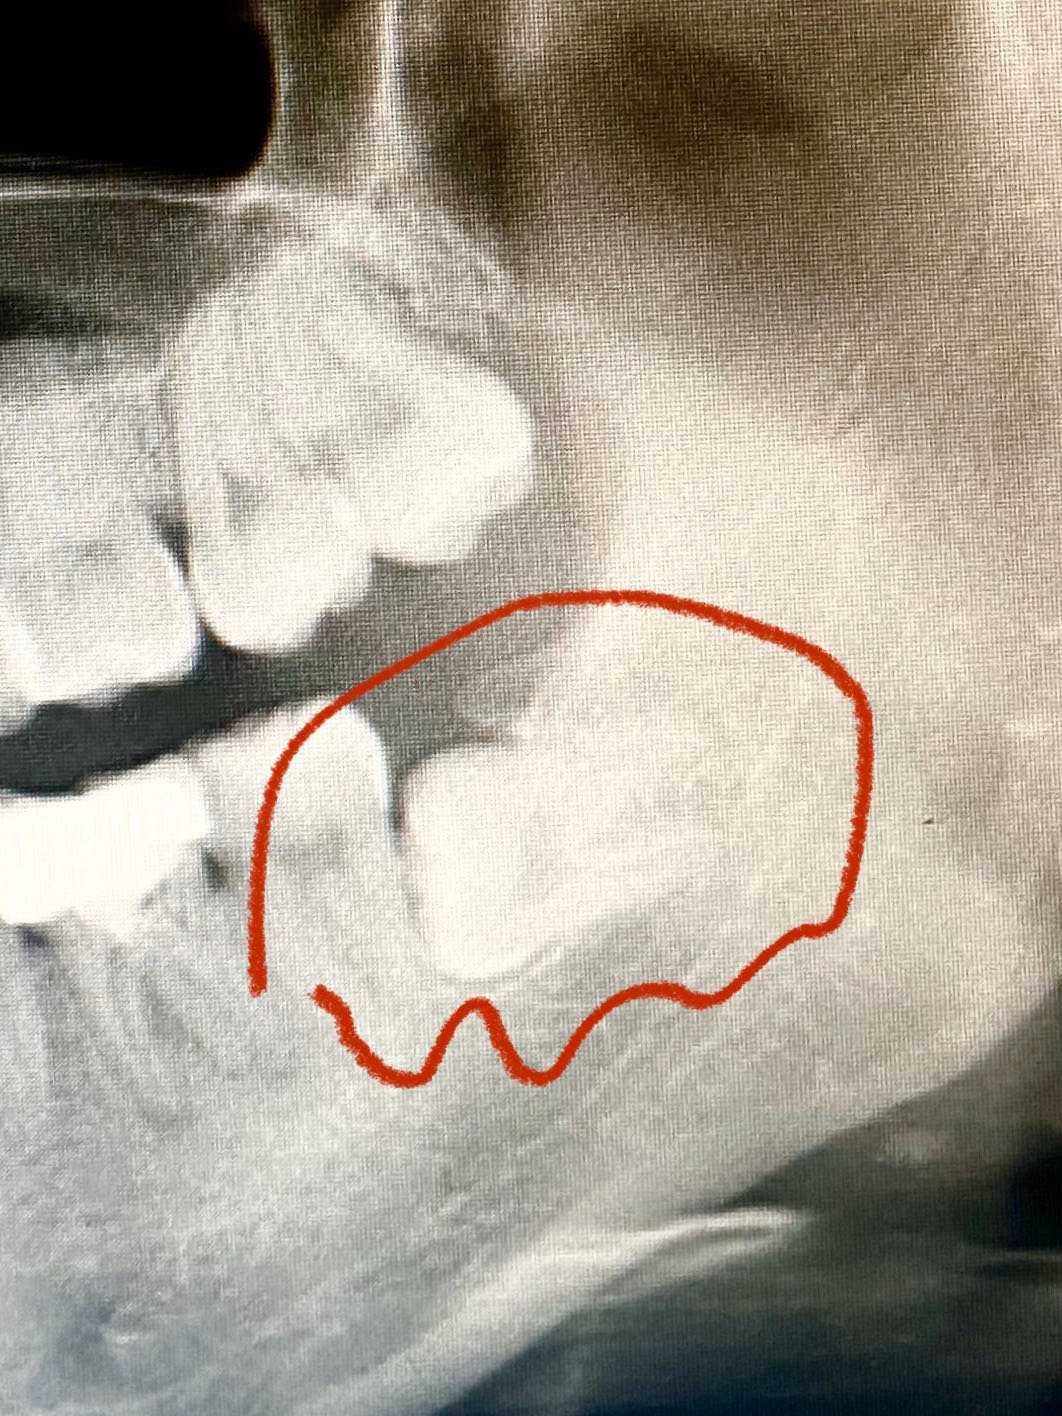

长了四颗智齿,下面两颗是全埋伏低位水平阻生,不疼,可以不拔吗?

【资源共享】第四磨牙一例